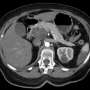

The drug, currently undergoing clinical trials, has shown remarkable results in shrinking tumors and extending patient lifespans. Medical experts are optimistic that this innovative treatment could become a game changer in the fight against pancreatic cancer, which is known for its low survival rates and late-stage diagnosis.

The urgency for new treatments is underscored by statistics showing that pancreatic cancer is the third deadliest cancer in the world. With only a 10% five-year survival rate, advancements like this are crucial for improving outcomes.